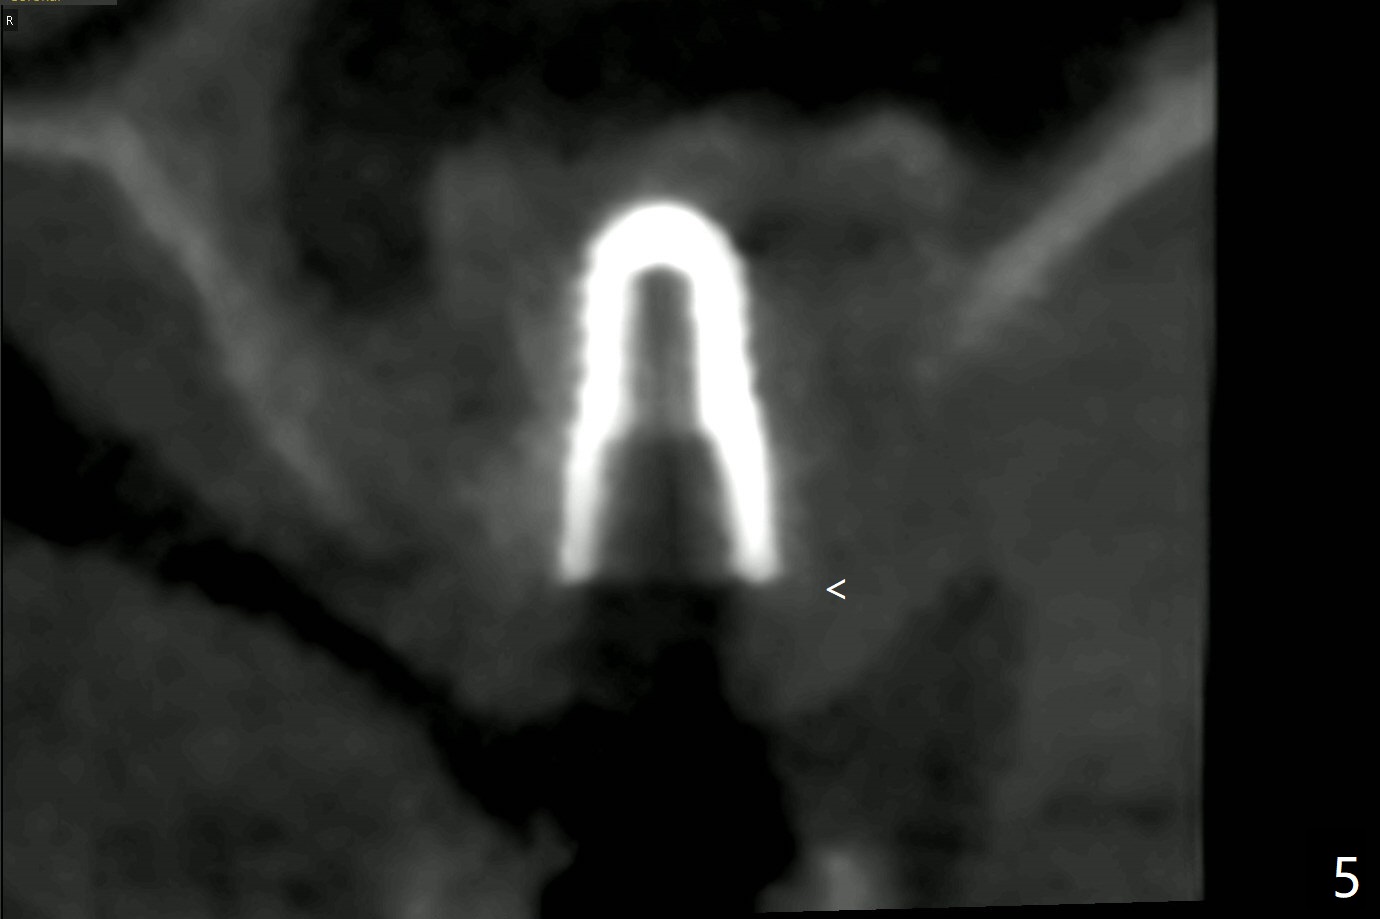

60岁男,左上6(牙根折裂严重骨质吸收)位点保存后6个月,回来植牙。术前CT显示骨质密度低,宽度足够,角化龈也宽,前后牙齿都有牙冠,制作导板麻烦,所以采纳徒手种植。使用4毫米活检打孔刀(Biopsy Punch)进入,简化手术,但是又怕开口不正,不敢用大号植体,术后CT发现钻洞偏颊侧。针对骨质密度低,使用1.2毫米钻头后(约8毫米),使用旋转式骨扩张器直至2.4/3.7毫米(图一(红虚线:原来骨质缺损)逐渐增加深度至11毫米),备洞几乎没有失去骨质,钻洞周围骨质密度谅必增高),取出最后一个扩大器后发现上颌窦底板破裂,放置粘性骨粉,使用4毫米报废植体做上颌窦提升,重复一次(图二,三),稳定性尚可。再次放置骨粉和PRF膜,使用正式植体提升(4.5x8毫米),临床上很难判断是否植体植入牙槽嵴之下(可能骨质疏松),只好拍摄CT(图四,五),好像正好牙槽嵴下,不过又植入骨粉一些(图七:*)。植体扭力~15Ncm,保险起见,放置愈合帽,表面放置少许骨粉以及打孔留下的牙龈(图六:G,之前一直泡在PRF上清液里),牙周胶水固定游离牙龈以及牙周敷料保护。术后6小时没有鼻出血。所以骨质缺损严重,植骨后,虽然缺损外形得到恢复,但是骨头质量,固定植体能力还不够。植牙时,需要适当改变手段,例如使用骨凿,提高骨质密度,而不是单纯使用钻头。术后病人恢复正常,没有疼痛,六天复诊,牙周敷料已经脱落,打孔的牙龈附着颊侧,部分骨粉暴露,但是看样子挺稳定,好像游离牙龈必须缝合。使用树脂敷料牢靠些。术后五周,伤口基本愈合,一处未愈合,与下面骨粉相通,用牙周探针稍微搅动,出血(图九)。擦干血迹,伤口还不错(图十)。术后2个月伤口好像正常愈合(图十一)。术后4.5个月根尖片显示6种植比5深,往后螺纹暴露可能性减少(图十二)。